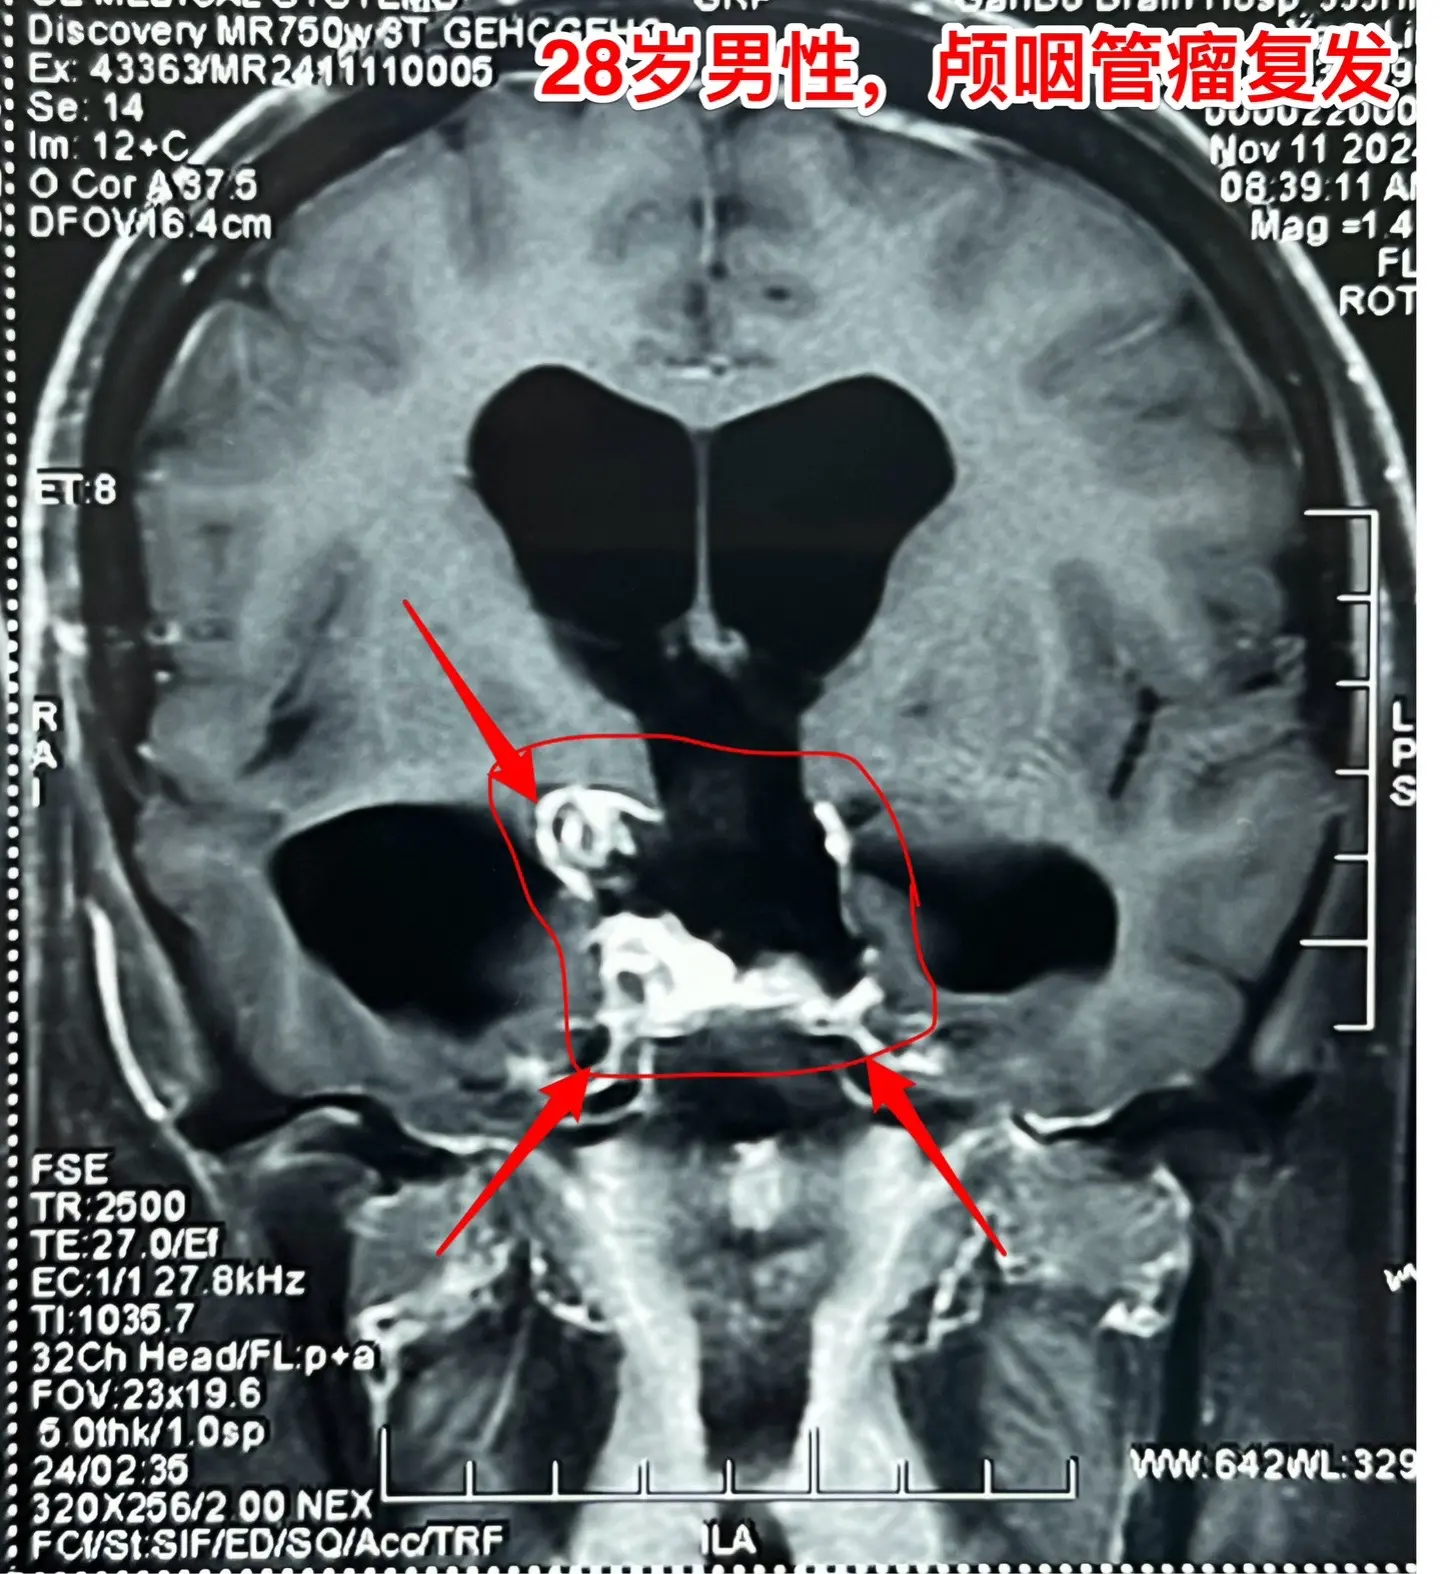

颅咽管瘤四次复发,为挽救视力只能作手术。28岁的四川小伙子,因颅咽管瘤在四川省先后作了四次开颅手术、一次脑室腹腔分流术。2024.6因肿瘤复发还作了一次伽马刀治疗,2024.9复查磁共振显示肿瘤体积在增大。 患者左眼已经失明了,右眼视力也在下降。为了挽救视力,他还是找我想再作一次手术,而且他的心态还是积极乐观的。 11月19日作了手术。原以为这个颅咽管瘤是不可能得到完全切除的,然而手术过程中却发现肿瘤不是一个整体,而是由四块肿瘤组成的,通过各个击破的方式将肿瘤完全切除了。病人右眼的视力也保住了。 希望肿瘤不再复发了!